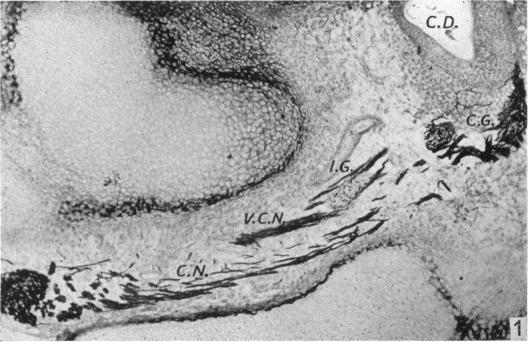

Nervous pathways in the developing human labyrinth.

J Anat. 1951 Oct;85(4):359-69.